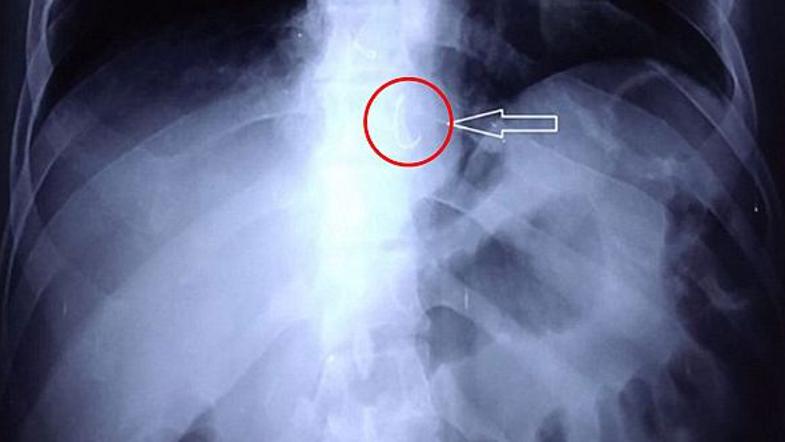

Zobna proteza Reševalni pas/Twitter

55-letni moški iz Indije je imel več dni težave zaradi kašlja, stiskanja v prsih in požiranja, zaradi česar se je odpravil k zdravniku in na svoje presenečenje ugotovil, kaj je bil resnični razlog. V požiralniku mu je zastal kos zobne proteze, ki jo je po nesreči požrl med spanjem, kar je razkrilo rentgensko slikanje.

Moški je sicer od otroštva trpel zaradi epileptičnih napadov, ki ga je doživel tudi teden dni, preden se je pojavila stiska v prsih. Po napadu je del odlomljene zobne proteze našel na tleh, iskal je še drugi del, a ga ni našel. Očitno je kos zobne proteze takrat po nesreči pogoltnil in mu je povzročala navedene zdravstvne težave.